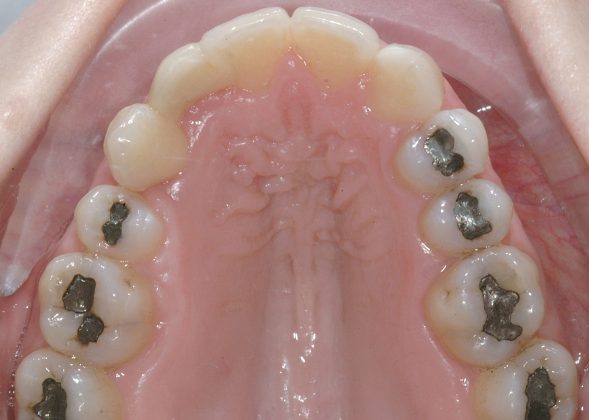

Al termine del trattamento ortodontico, che ha richiesto 24 mesi di terapia, è stata applicata una contenzione fissa3 all’arcata inferiore mediante filo multi-intrecciato coassiale .0195” esteso da 4.4 a 3.5 al fine non solo di stabilizzare il risultato sia sul piano orizzontale sia verticale, ma soprattutto per prevenire adeguatamente l’affollamento dentale terziario (Figure 9a-e).

All’arcata superiore è stato mantenuto il pontic in composito in sede 1.2, poiché la paziente, per esigenze personali, aveva preferito rimandare a un tempo successivo la sostituzione implantare di 1.2 agenesico, così come la coronoplastica definitiva di 2.3.

Dopo tre anni dal termine del trattamento ortodontico, la paziente ha richiesto di finalizzare il suo caso; è dunque stata effettuata la sostituzione implanto-protesica dell’elemento 1.2, senza necessità di ulteriori rifiniture ortodontiche, avendo mantenuto, grazie al pontic in composito, un ottimo parallelismo radicolare tra 1.1 e 1.3.

È stata eseguita contestuale terapia rigenerativa, per ottimizzare qualità e quantità dei tessuti nel sito implantare. Come si rileva dalle immagini di follow up, dopo la fase implanto-protesica superiore, è stata applicata anche una parziale contenzione fissa tra gli incisivi centrali superiori e il risultato ortodontico si è mantenuto stabile nel tempo (Figure 10 a-e).